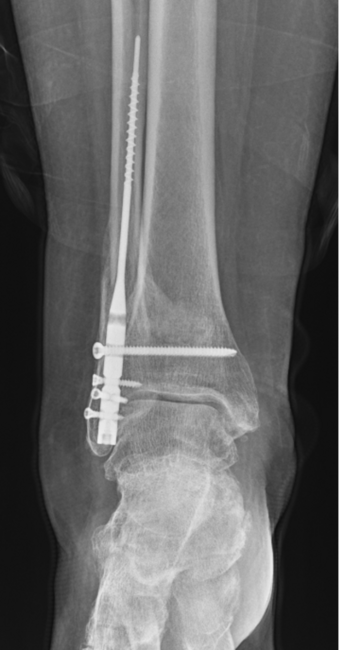

Acute Tibiotalocalcaneal Intramedullary Nailing

Intramedullary tibiotalocalcaneal (TTC) nailing is an established and well-accepted surgical option for degenerative hindfoot and ankle arthritis and for deformities such as Charcot arthropathy. Indications for use have expanded to acute trauma such as ankle and pilon fractures. As a load-sharing implant, this option provides a biomechanically stable construct with minimal soft tissue disruption with the allowance of early weight bearing which is particularly beneficial for the geriatric population. The goal with this fixation construct is stabilization of the operative limb, rather than anatomic reduction.

Georgiannos and colleagues performed a prospective randomized control study comparing TTC arthrodesis versus ORIF in fragility fractures of the elderly. They found equivalent functional outcomes and significantly lower revision rates in the TTC group.16 In contrast, Large and team compared TTC fusion with ORIF in elderly ankle fractures with at least 1 high-risk comorbidity. They found no significant differences in re-operation, infection or union rates between the cohorts.17 While TTC arthrodesis is a viable option for patients, significant complications can arise. Lu and coworkers found high complication rates following TTC arthrodesis in elderly patients with 10% superficial infection, 8% deep infection, 11% implant failure, 11% malunion and 27% all-cause mortality in a high-risk patient cohort with a mean age of 78 years and a diabetes mellitus prevalence rate of 42%.18 Again, a holistic approach should be taken to geriatric patient care, and acute hindfoot intramedullary nailing may best be served for low demand patients with significant comorbidities. Srinath and team developed a framework for choosing hindfoot nailing over standard open reduction internal fixation in the geriatric population. They determined hindfoot nailing is most reasonable in patients with cognitive impairment, uncontrolled diabetes, ASA >2, soft tissue compromise surrounding the ankle, and declining independent mobility.19